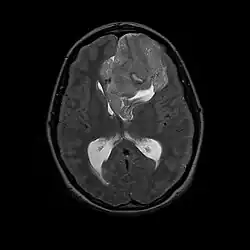

Als Neurozytom wird ein seltener gutartiger Hirntumor bezeichnet. Da Rezidive auftreten können, wird der Tumor nach der WHO-Klassifikation der Tumoren des zentralen Nervensystems als Grad II eingeordnet. Die WHO-Klassifikation unterscheidet das typischerweise intraventrikulär im Bereich des Foramen Monroi gelegene zentrale Neurozytom vom selteneren extraventrikulären Neurozytom, das keinen Bezug zum Ventrikelsystem des Gehirns besitzt.

Neurozytome sind selten. Seit der Erstbeschreibung im Jahre 1982[1] sind weltweit einige 100 Fälle berichtet worden. Das zentrale Neurozytom führt aufgrund seiner intraventrikulären Lage typischerweise zu einer Behinderung des Liquorabflusses und macht sich klinisch als Hydrocephalus bemerkbar. In der Bildgebung stellen sich Neurozytome als nicht selten zystische, variabel Kontrastmittel aufnehmende Raumforderungen dar.